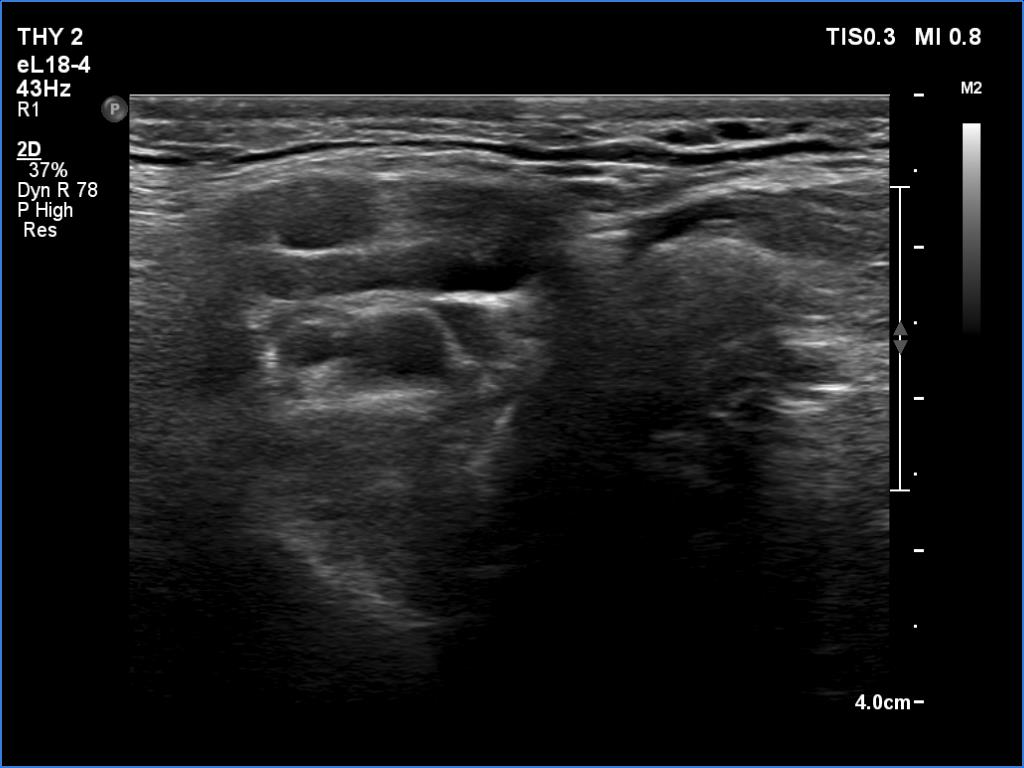

Ultrasonography revealed a hypoechogenic nodule in the ventromedial part of the left lobe. The nodule had irregular borders, contained microcalcifications and displayed perinodular and irregular intranodular blood flow.

Ultrasonography revealed hypoechoic discrete lesions in both thyroid lobes. The lesions presented microcalcifications. Corresponding to the palpable mass in the right submandibular region, a reactive-type regular lymph node was found. There was an enlarged lymph node in the left submandibular region. The node had a regular hilum but displayed a heterogeneous pattern.